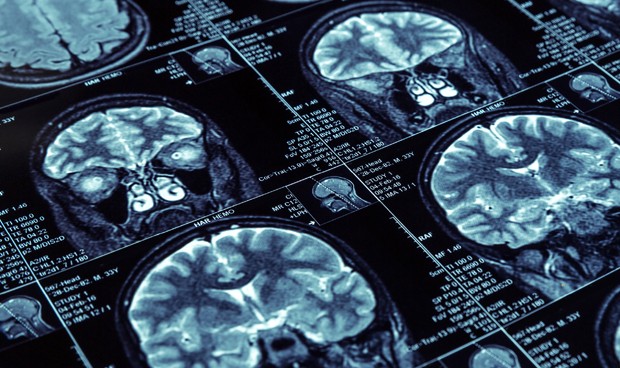

Investigadores de Cambridge (Reino Unido) han realizado el primer análisis exhaustivo de los genes que se expresan en células cerebrales individuales de pacientes con alzhéimer, ofreciendo así un mapa completo de cómo la enfermedad afecta al cerebro.

Los investigadores analizaron muestras de cerebro postmortem de 24 personas que mostraron altos niveles de patología de la enfermedad de Alzheimer y 24 personas de edad similar que no tenían estos signos de enfermedad. Los investigadores también tenían datos sobre el rendimiento de los sujetos en las pruebas cognitivas.

El equipo realizó una secuenciación de ARN de una sola célula en aproximadamente 80.000 células de los participantes. "Los estudios previos de expresión génica en pacientes con alzhéimer han medido los niveles generales de ARN en una sección del tejido cerebral, pero estos estudios no distinguen entre los tipos de células, lo que puede enmascarar los cambios que ocurren en tipos de células menos abundantes", han explicado los autores.

Usando el enfoque de la secuenciación de una sola célula, los investigadores pudieron analizar no solo los tipos de células más abundantes, que incluyen neuronas excitadoras e inhibidoras, sino también células cerebrales no neuronales más raras, como oligodendrocitos, astrocitos y microglia. Los investigadores descubrieron que cada uno de estos tipos de células mostraba distintas diferencias en la expresión génica en los pacientes con alzhéimer.

De hecho, usando un conjunto de imágenes de resonancia magnética de 500 sujetos adicionales del grupo de estudio de órdenes religiosas, los investigadores encontraron que las mujeres con graves déficits de memoria tenían mucho más daño de la sustancia blanca que los pacientes hombres emparejados.